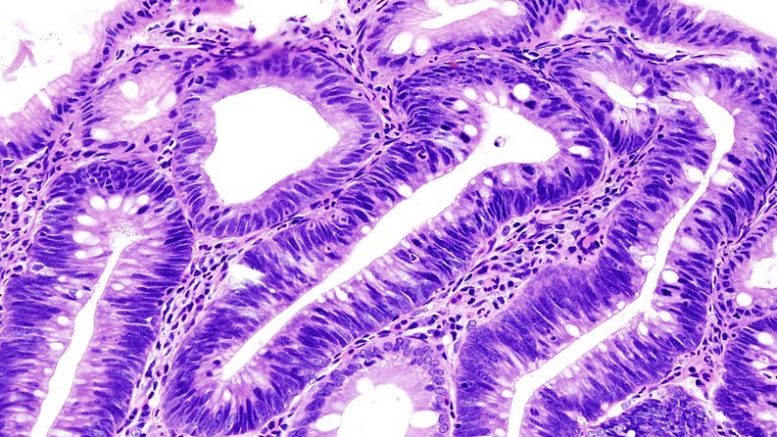

La Sindrome Metabolica è un importante fattore di rischio per la insorgenza di adenomi e cancro del colon. Lo dimostra uno studio coordinato da ricercatori della Ud’A coordinati dal prof. Matteo Neri, ordinario presso il Dipartimento di Medicina e Scienze dell’Invecchiamento.

Il lavoro è stato appena pubblicato sulla prestigiosa rivista SAGE Journals. “Sebbene fosse noto in passato che obesità e diabete conclamati fossero tra i fattori di rischio per le neoplasie del colon, – spiega il prof. Matteo Neri – abbiamo dimostrato che anche soggetti normopeso e prediabetici, se posseggono tre delle cinque componenti della sindrome metabolica, sono a rischio doppio rispetto a chi non le possiede di sviluppare adenomi o carcinoma del colon. La sindrome metabolica è un insieme di caratteristiche antropometriche (circonferenza addominale), circolatorie (pressione arteriosa) e laboratoristiche (glicemia, trigliceridemia, colesterolemia) la cui presenza è un fattore di rischio noto per le malattie cardiovascolari e, da oggi, anche per le neoplasie del colon, indipendentemente dalla presenza di obesità. La forza di questo studio – prosegue il prof. Neri – risiede nell’elevato numero di soggetti coinvolti per l’esame colonscopico (circa 6.000) che ha portato a riscontrare 213 carcinomi e complessivamente 1949 polipi. Questo imponente numero di soggetti arruolati è stato ottenuto grazie al coinvolgimento di 50 centri di Endoscopia Digestiva distribuiti su tutto il territorio italiano e rappresentativi della nazione. Ad oggi il fattore di rischio più importante per le neoplasie del colon è l’età. Tutti i programmi di screening si basano sul reclutamento di soggetti con più di 50 anni. In realtà il riscontro di neoplasie prima di questa età è in crescente aumento. Questo studio dimostra che la sindrome metabolica è un fattore di rischio indipendente per neoplasie del colon soprattutto in soggetti con meno di 50 anni. Ciò – conclude il prof. Neri – indica la necessità di un possibile mutamento delle strategie di screening delle neoplasie del colon su base nazionale o regionale che includano questo fattore di rischio.”